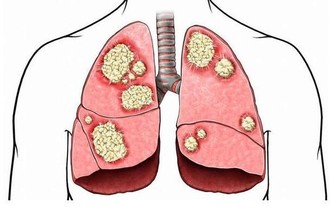

2. 他氣喘吁籲

氣喘可能是由於過於肥胖、心血管問題或癌症,三者都很嚴重。超重是比高血壓和高膽固醇更危險的,它能導致全方位的高死亡率健康問題,所以不容忽視。